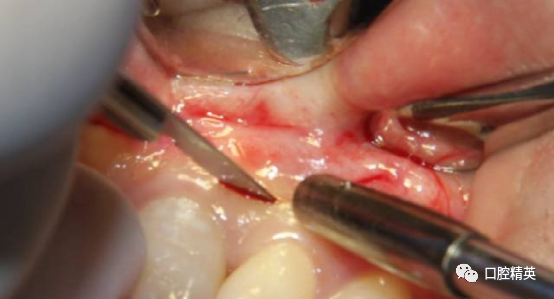

保留美学区域软组织及其附着

边角区轻柔翻全厚瓣,始终以轻柔动作处理软组织瓣并保湿。由两侧向中上方向翻开。